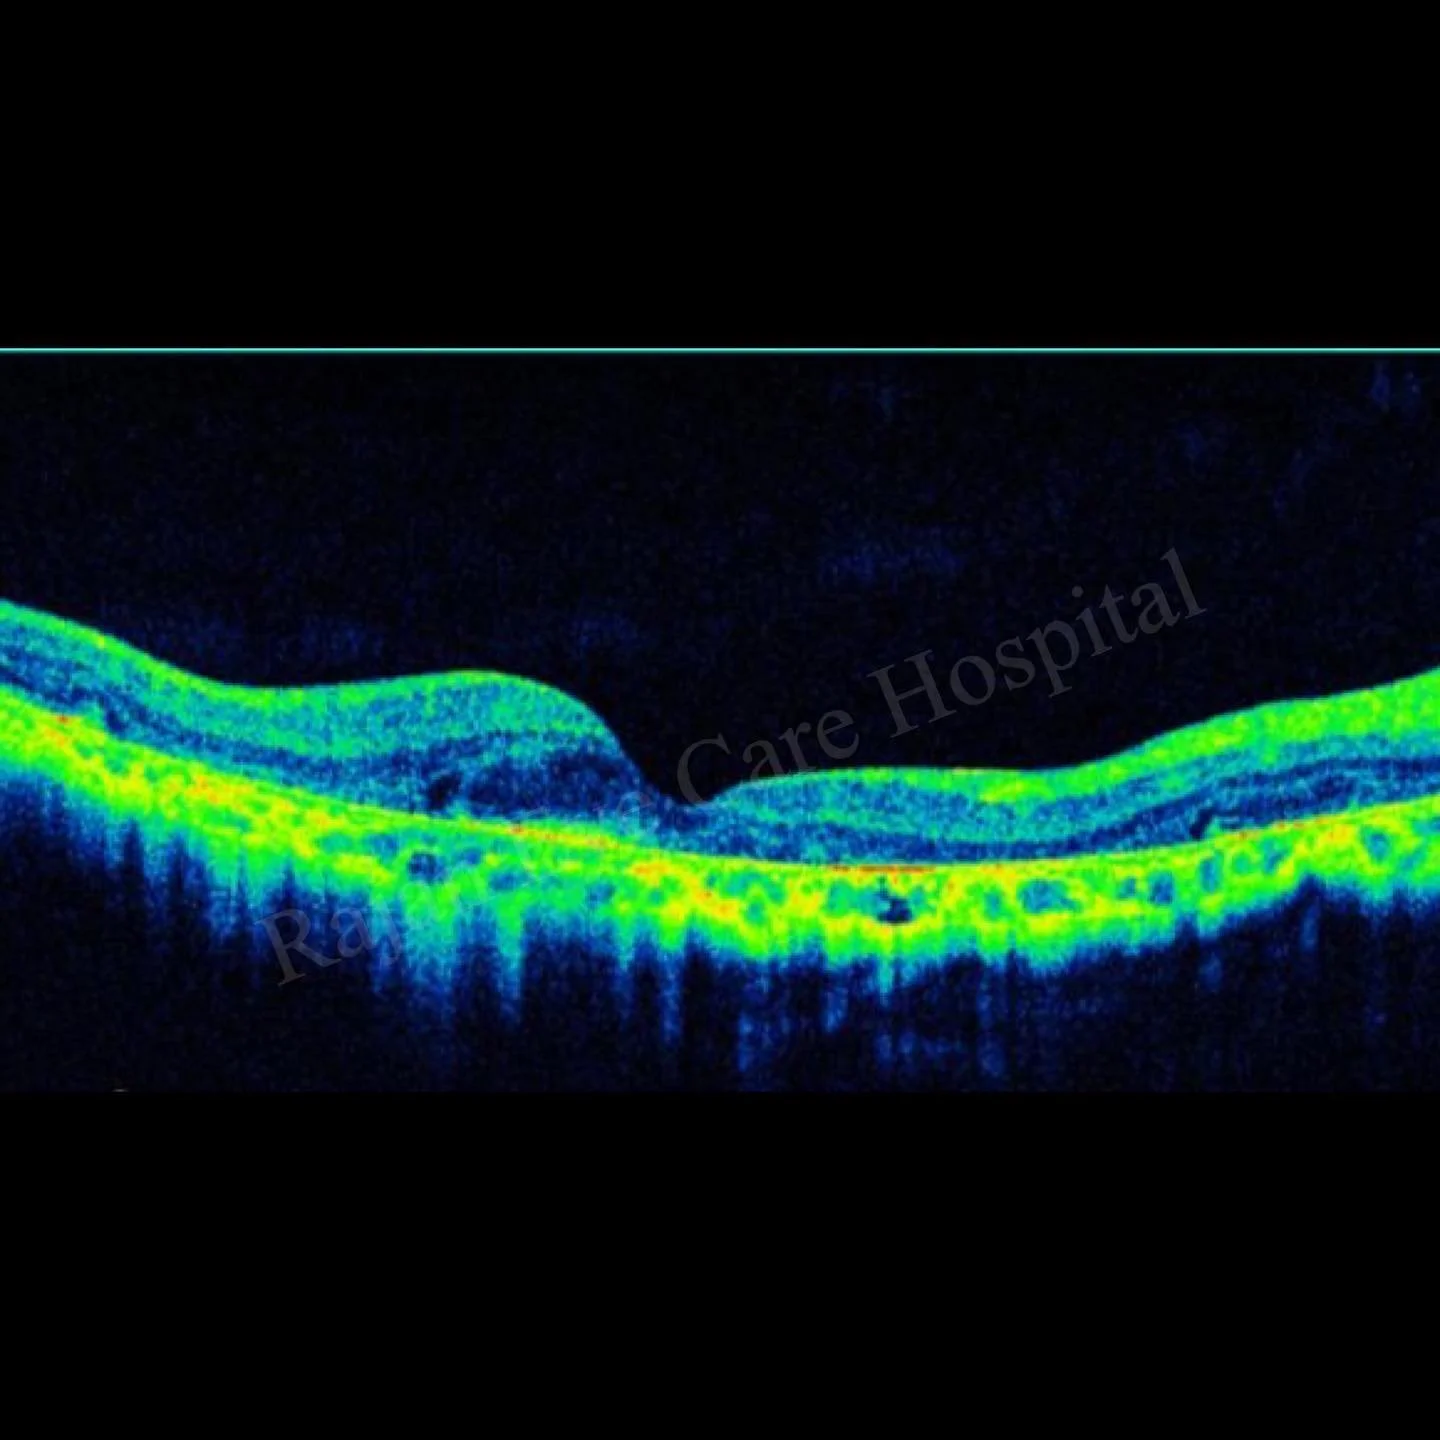

๐™Š๐˜พ๐™ :โฃ

โ— Shows atrophic changes and disorganisation in photoreceptorsโฃ

โ— RPE and lipofuscin deposits maybe detected within the parafoveal RPE.โฃ